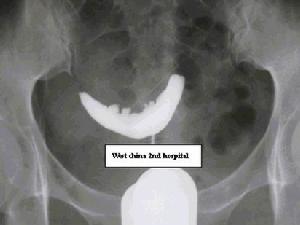

五、子宫输卵管造影

照1 子宫肌瘤的子宫造影象(子宫右角粘膜下肌瘤造影象,显示该部充盈缺损)理想的子宫造影不但可显示粘膜下肌瘤的数目、大小,且能定位。因此,对粘膜下肌瘤的早期诊断有很大帮助,而且方法简单。有肌瘤处造影摄片显示宫腔内有充盈残缺(照1)。